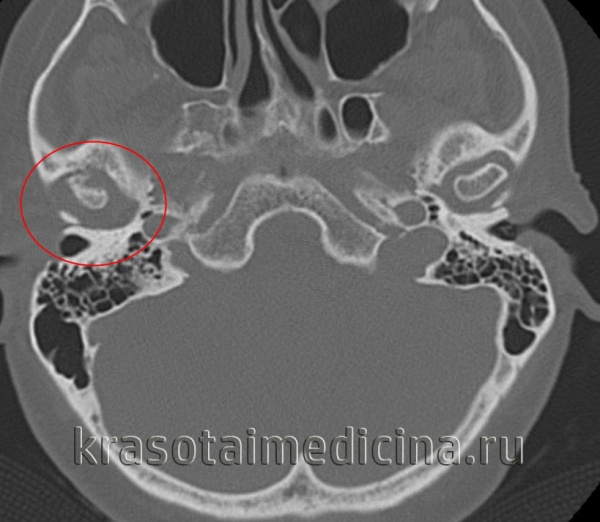

КТ ВНЧС. Артроз правого височно-нижнечелюстного сустава: деформация мыщелка нижней челюсти, сужение суставной «щели», остеофиты.